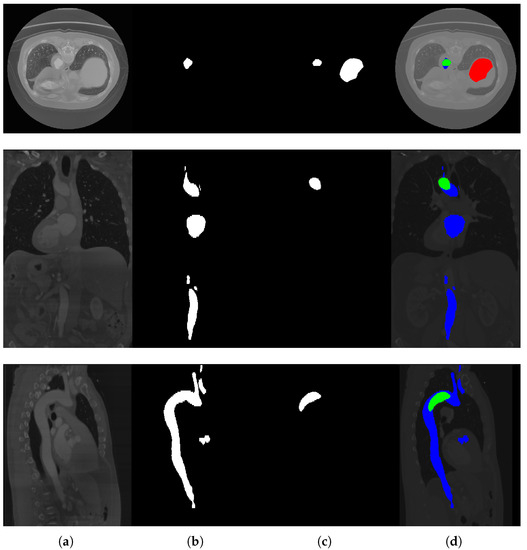

The results obtained are promising but limited by the quality of the annotations. Indeed, the ground truth of the dataset was obtained with a semi-automatic procedure and, in some cases, was not completely accurate. However, the dataset was provided with a reasonable supervision that somehow compensates for the absence of datasets with aortic images labeled at the pixel level. In Figure 5, some images are provided, together with their labels and the segmentation generated by the network, for a qualitative evaluation. Figure 6 shows some slices not correctly segmented by the network. As we can see, in this case, the images are actually difficult to interpret; in the second and third row, in fact, the slices are really dark and, in the first row, the network probably wrongly classified the aorta due to its size.

Figure 6.

Some erroneous segmentation results. In (d), green represents correctly predicted pixels, blue pixels are present in the label but not predicted as aorta from the network, and red pixels are incorrectly predicted as aorta. (a) Original images; (b) Ground truths; (c) Network predictions; (d) Predictions overlapped with labels and pre-processed original images.